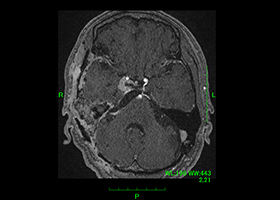

2. 良性脳腫瘍の外科治療

当科では主に髄膜腫および神経鞘腫の治療に力を入れています。

① 髄膜腫(特に頭蓋底部)

髄膜腫は脳を覆っている硬膜という組織から発生する良性腫瘍です。脳表にできたものは摘出が容易ですが、脳深部(特に頭蓋底部)にできたものは脳実質や神経、血管を巻き込みながら腫瘍が存在しているので摘出は困難です。当科では術中ナビゲーションシステムや神経生理学的モニタリングを使用しながら安全かつ効率的な手術を行っています。

症例1)65歳男性、頭蓋底部巨大髄膜腫、外科手術のみ

[画像所見]

MRI造影検査で巨大脳腫瘍を認めます。